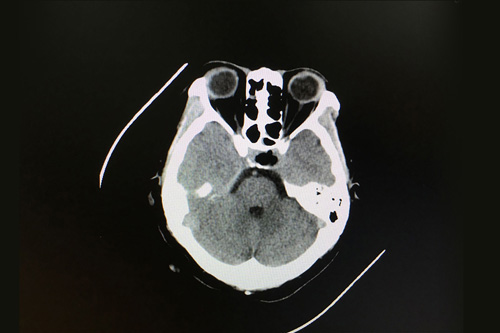

术前影像显示:垂体占位,不排除垂体瘤囊性变

这时,从患者影像资料上来看,颅内鞍区的肿物大小为1.3cm*2cm*0.8cm,可以确认是鞍区良性肿瘤,垂体瘤囊变的可能性较大,有压迫视神经的迹象。性激素检查发现患者垂体泌乳素分泌很高,超出参考值范围55个单位。占位引起高颅压,压迫神经,造成患者额头和两侧颞部疼痛明显,眼睛也出现胀痛症状,已严重影响到其生活。各位专家会诊结果:垂体瘤囊变符合手术指征,应尽快安排手术。做了手术会尽快解除压迫,垂体激素分泌也会逐步回归正常。

患者术后影像:鞍区肿瘤术后改变,脑内未见明显异常